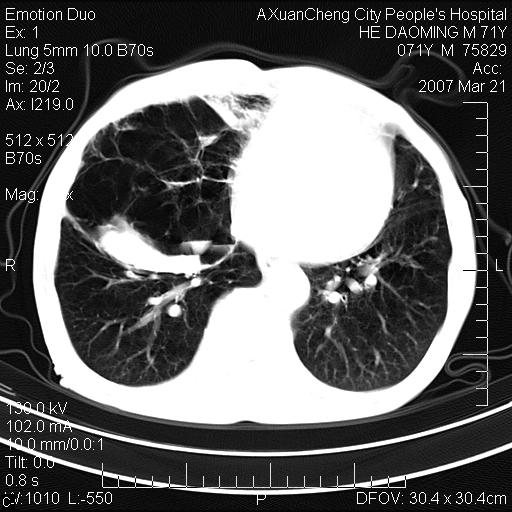

标题: CT7269:[原创] 咳嗽,咳痰,大家讨论右肺病变的部位 [打印本页]

标题: CT7269:[原创] 咳嗽,咳痰,大家讨论右肺病变的部位

1.慢支肺气肿 肺心病 肺大泡;2.叶间裂积液,前胸膜粘连

右侧相当于叶间软组织样密度ct值约50hu,请大家讨论是什么性者病变

右下肺大囊肿伴感染.肺气肿,肺大泡.

考虑:慢性支气管炎合并全小型肺气肿、肺大泡、间质纤维化、感染,右斜裂积液。

考虑慢支,肺气肿,肺大泡,间质纤维化;右侧斜裂液气胸考虑(可能因为肺大泡破裂破入斜裂所致).

考虑病变以右上中肺多发肺大泡为主并感染。请结合临床考虑慢支肺气肿,肺心病。

1双肺慢性支气管炎并全小叶型肺气肿肺大泡2间质性纤维化3右侧斜裂积液

考虑:慢性支气管炎合并右侧全小型肺气肿、肺大泡并感染、双肺间质纤维化,右斜裂积液。

如果患者变化一下体位扫描可分辨液平与斜裂的关系。